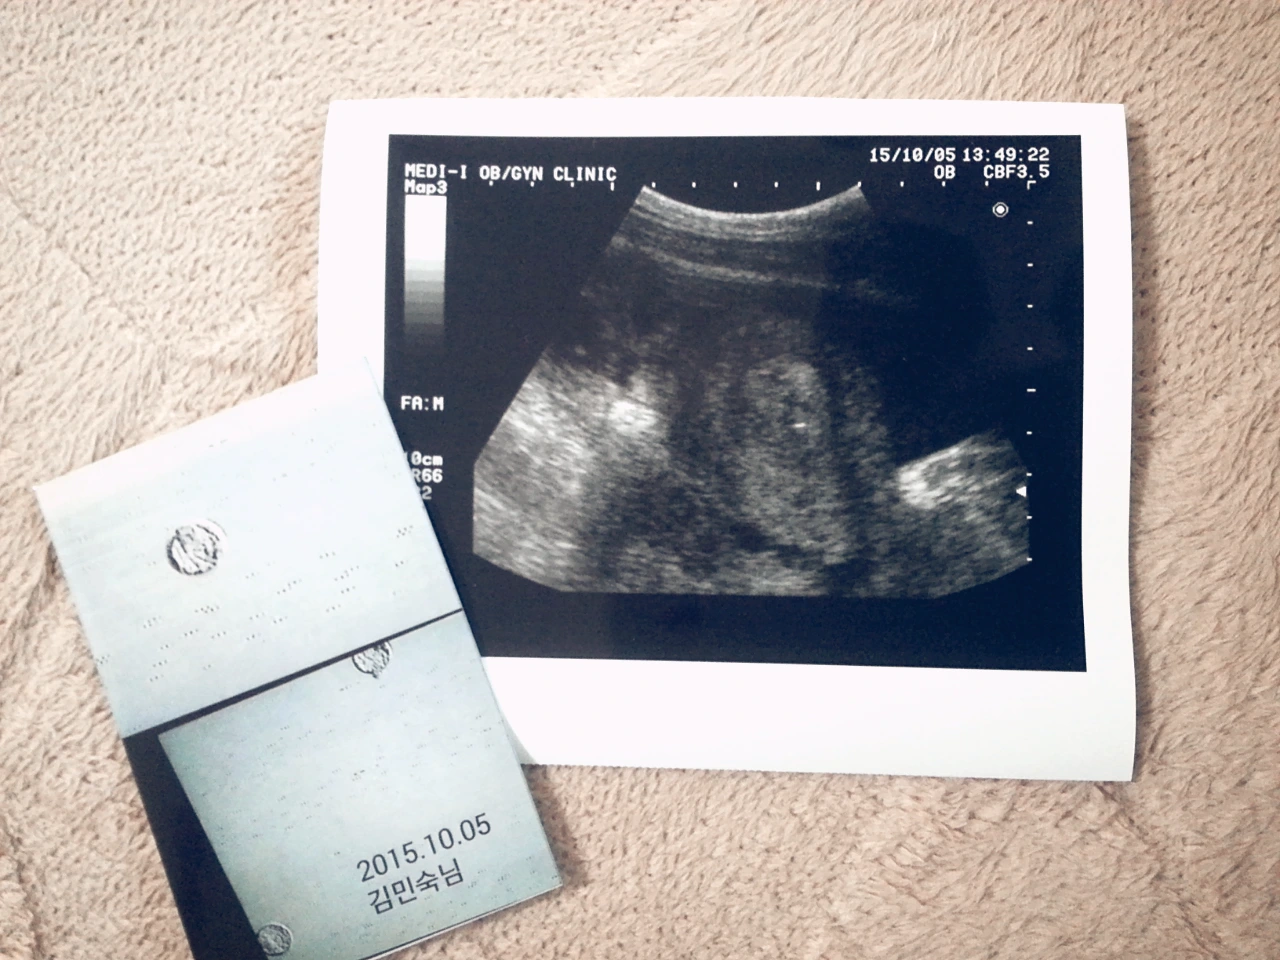

총 36개의 채취된 난자 중에서 30개의 성숙 난자가 있었고, 그중에서 20개의 양호한 수정란을 얻었다고 한다. 17개는 냉동시켰고 3개는 이식했다. 그 3개가 바로 위에 사진이다. 검은 초음파 사진이 자궁인데, 중간에 작고 밝게 빛나는 점이 이식된 수정란들이다. 오늘내일 안정하고, 다음 주 월요일에 임신 여부 피검사를 할 예정이다. 인터넷 검색을 해보니까 시체놀이를 하라고 되어 있던데, 나랑은 안 맞나 보다. 허리가 너무 아프다. 그래도 집에 와서 좀 뒹굴뒹굴하다가 남편 퇴근시간이 다가와 앉아있다. 티브이를 볼까, 책을 읽을까 하다가 그냥 멍하니 앉아 있다.